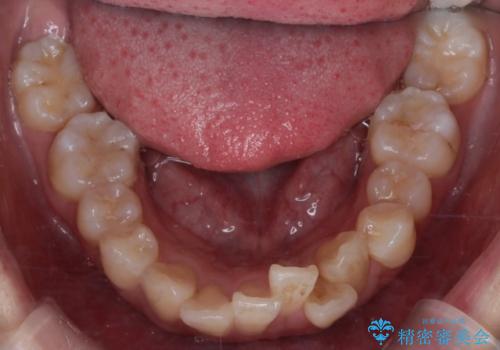

- 八重歯(叢生)と、上下の歯の中心線(正中)がずれていることを主訴にご来院されました。精密な検査の結果、歯列全体のスペースが大幅に不足しており、八重歯を正しい位置に配列し、正中のズレを改善するためには、上下左右の第一小臼歯を抜歯する必要があると診断。装置には、目立ちにくい審美ワイヤーを使用し、見た目を気にせず、機能性と審美性が完璧に整った咬み合わせを目指す治療計画を立案しました。

今回の矯正治療では、まず計画通り上下左右の小臼歯4本を抜歯し、八重歯や正中のズレを解消するための十分なスペースを確保しました。装置には、目立ちにくい白いブラケットとワイヤーを使用した審美ワイヤー矯正を採用。

八重歯: 突出していた八重歯を歯列内に誘導し、デコボコを解消しました。

正中のズレ: 歯を左右対称に移動させることで、上下の歯の中心線を正確に合わせ、顔全体のバランスも改善しました。